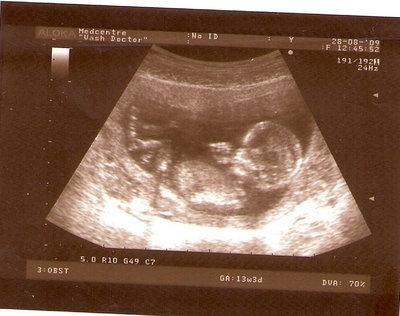

13 НЕД И 5 ДНЕЙ

| Вложения: |

3.jpg [ 96.81 КБ | Просмотров: 2446 ]

Nikisa писал(а): Foto prosto chudesnoe. A na kakom sroke uznali, chto sin.............. НА 13 НЕДЕЛЯХ.КАК РАЗ ВОТ В ЭТО узи, ОНО УМЕНЯ ВТОРОЕ БЫЛО. ЭТО КОНЕЧНО МАЛЕНЬКИЙ СРОК ДЛЯ ОПРЕДЕЛЕНИЯ ПОЛА. НО Я ПОПРОСИЛА ВРАЧА(ЭТО КТСТАТИВ РОССИИ БЫЛО) ХОТЯ БЫ ПРЕДПОЛОЖИТЬ. ЕЙ ВСЁ ТАКИ УДАЛОСЬ РАССМОТРЕТЬ.НУ ВООБЩЕМ ЧЕРЕЗ НЕСКОЛЬ ДНЕЙ ПОЙДУ К ВРАЧУ, УЖЕ АМЕРЕКАНСКОМУ И УЗНАЮ ТОЧНО. К ТОМУ ВРЕМЕНИ У МЕНЯ БУДЕТ СРОК 18 НЕДЕЛЬ. ХОТЕЛОСЬ БЫ ПОСМОТРЕТЬ НА ДРУГИЕ ФОТО НА ЭТОМ СРОКЕ ИЛИ БОЛЬШЕ. ТАК ЧТО ВЫКЛАДЫВАЙТЕ, ЕСЛИ НЕ ЖАЛКО!